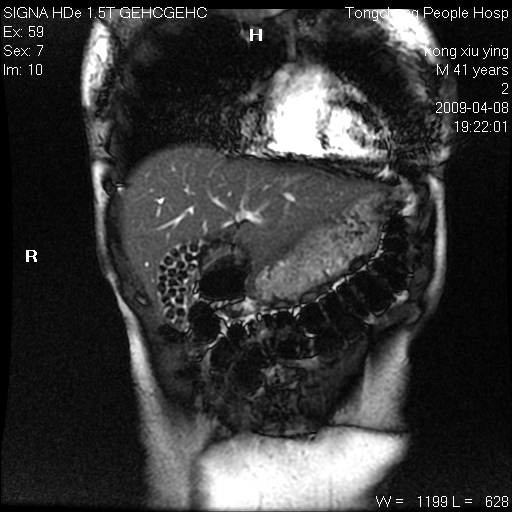

标题: CL1008:【经典】胆囊石榴籽样结石。

女,41岁。健康体检——彩超提示:胆囊显示不清。平素健康,无不适感。

腹部mr扫描及mrcp,图像如下: